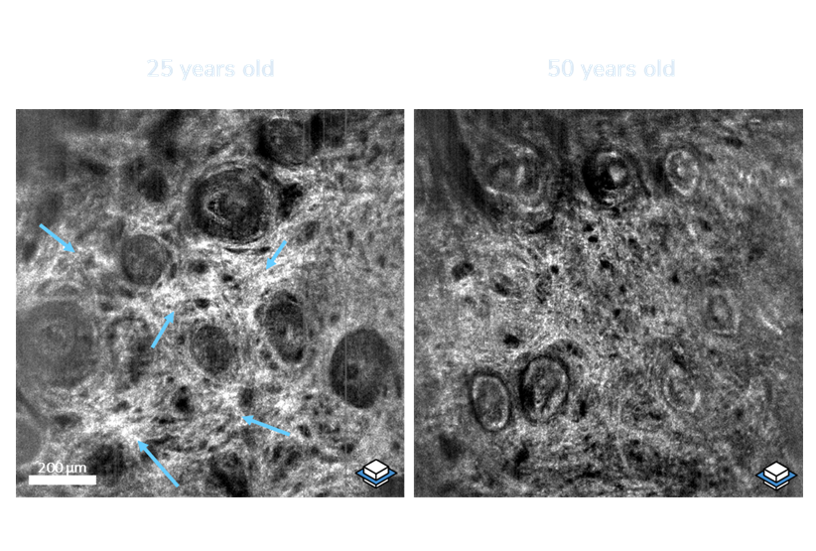

deepLive™ integrates LC-OCT (Line-field Confocal Optical Coherence Tomography) technology which provides a unique 3D imaging modality, allowing the user to switch from a histology-like vertical mode to a confocal-like horizontal mode,

and to record a 3D stack of tissue volumes in situ.

Quantitative skin analyses

adapted to your studies